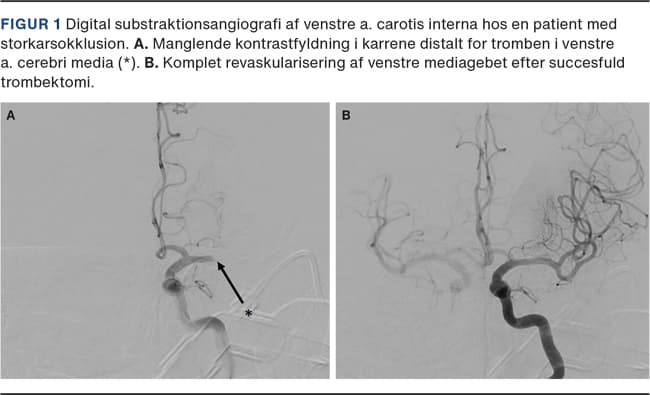

I forlængelse af de mange observationelle studier, der overordnet taler for en fordelagtig effekt af trombolyse, blev der gennemgået data fra den danske database, Dansk Apopleksi Register (DAP) [20]. Med afsæt i DAP blev der udført et retrospektivt studie, hvor man inkluderede patienter, der havde iskæmisk apopleksi og var behandlet med trombektomi med eller uden trombolyseforbehandling på Aarhus Universitetshospital i perioden 2015-2019 [21]. Baseret på administration af trombolyse blev patienterne inddelt i to behandlingsgrupper: En gruppe, der fik kombineret terapi med trombolyse og trombektomi, og en gruppe, der fik trombektomi alene. Det primære udfald var godt funktionelt udfald efter 90 dage defineret som modified Rankin Scale (mRS)-score 0-2 (selvhjulpen i daglige gøremål), og det sekundære udfald var succesfuld reperfusion defineret som modified thrombolysis in cerebral infarction scale (mTICI)-score 2b-3 (reperfusion af mere end halvdelen af det tidligere infarcerede område). I Figur 1 ses en patient, der havde M1-okklusion og efter trombektomi opnåede fuld reperfusion.

Patienterne i de to behandlingsgrupper adskilte sig ikke mht. alder eller apopleksiens sværhedsgrad, men der var en forsinkelse i ankomst til lyskepunktur på 8 min i gruppen, der fik kombineret terapi. Den statistiske sammenligning viste, at der var en signifikant højere andel af patienter med godt funktionelt udfald (57,1% vs. 38,8%, p < 0,0001) og succesfuld reperfusion (85,6% vs. 78,8%, p = 0,007) i gruppen, der fik kombineret terapi, end i gruppen, der fik trombektomi alene (Tabel 1). De patienter, der blev behandlet med kombineret terapi, klarede sig altså bedre end de patienter, der blev behandlet med trombektomi alene (Figur 2).